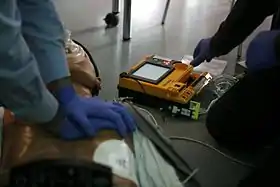

Defibrillators produce a defibrillation (electric shocks) that can restore the normal heart function of the victim.

Nevertheless, they are only indicated for some arrhythmias (abnormal heart beatings), specifically ventricular fibrillation (VF) and pulseless ventricular tachycardia. Defibrillation is not indicated if the patient is conscious or has a normal pulse. Defibrillation is also not indicated if the heart has completely stopped, as in asystole or pulseless electrical activity (PEA), in those cases a normal CPR would be used to oxygenate the brain until the heart function can be restored. Improperly given electrical shocks can cause dangerous arrhythmias, such as the ventricular fibrillation (VF).[45]

The standard defibrillation device, prepared for a fast use out of the medical centres, is the automated external defibrillator (AED), a portable machine of small size (similar to a briefcase) that can be used by any user with no previous training. That machine produces recorded voice instructions that guide to the user along the defibrillation process. It also checks the victim's condition to apply automatically electric shocks at a correct level, if they are needed. Other models are semi-automatic and need that the user push a button before producing an electric shock.

The defibrillation process is simple, but there exist written instructions of defibrillators that explain it step-by-step.

There are several devices for improving CPR but, only defibrillators (as of 2010) have been found better than standard CPR for an out-of-hospital cardiac arrest.[5]